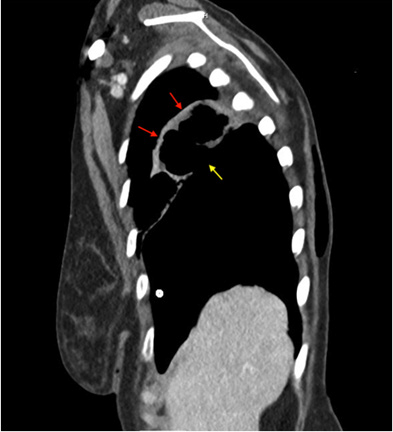

On day 2 of admission, the patient was comfortable still on supplemental oxygen to address the atelectasis and morning vital signs were all within normal limits. On routine bedside chest exam was done and yielded righ-sided, harsh, bronchial breathing and hyperresonance on percussion that were not present on admission. These findings prompted an emergent chest x-ray which showed a massive right sided pneumothorax with right lung atelectasis and mediastinal shift to the left. Ath that time, the surgery service was consulted and a pigtail chest tube was placed. Post-tube-placement chest x-ray suggested an initial slight improvement of the pneumothorax. However, after two days with her chest tube intact, serial chest x-rays failed to show any appreciable improvement of the size of the pneumothorax. To further investigate the persistence of the pneumotorax, a thorax CT was ordered and showed confluence of the lower border of the cavitary lesion with the right pleural space and tethering of tissue to the right sided chest wall pleura highly suggestive of an alveolarpleural fisutla (Figures 4-7).

Figure 4: Single view chest X-ray showing Right pneumothorax with collapsed right lung; Red arrows, and left mediastinal shift; red arrow heads. Persistent Cavitary lesion with tethering of right lung tissue to chest wall; white arrows.